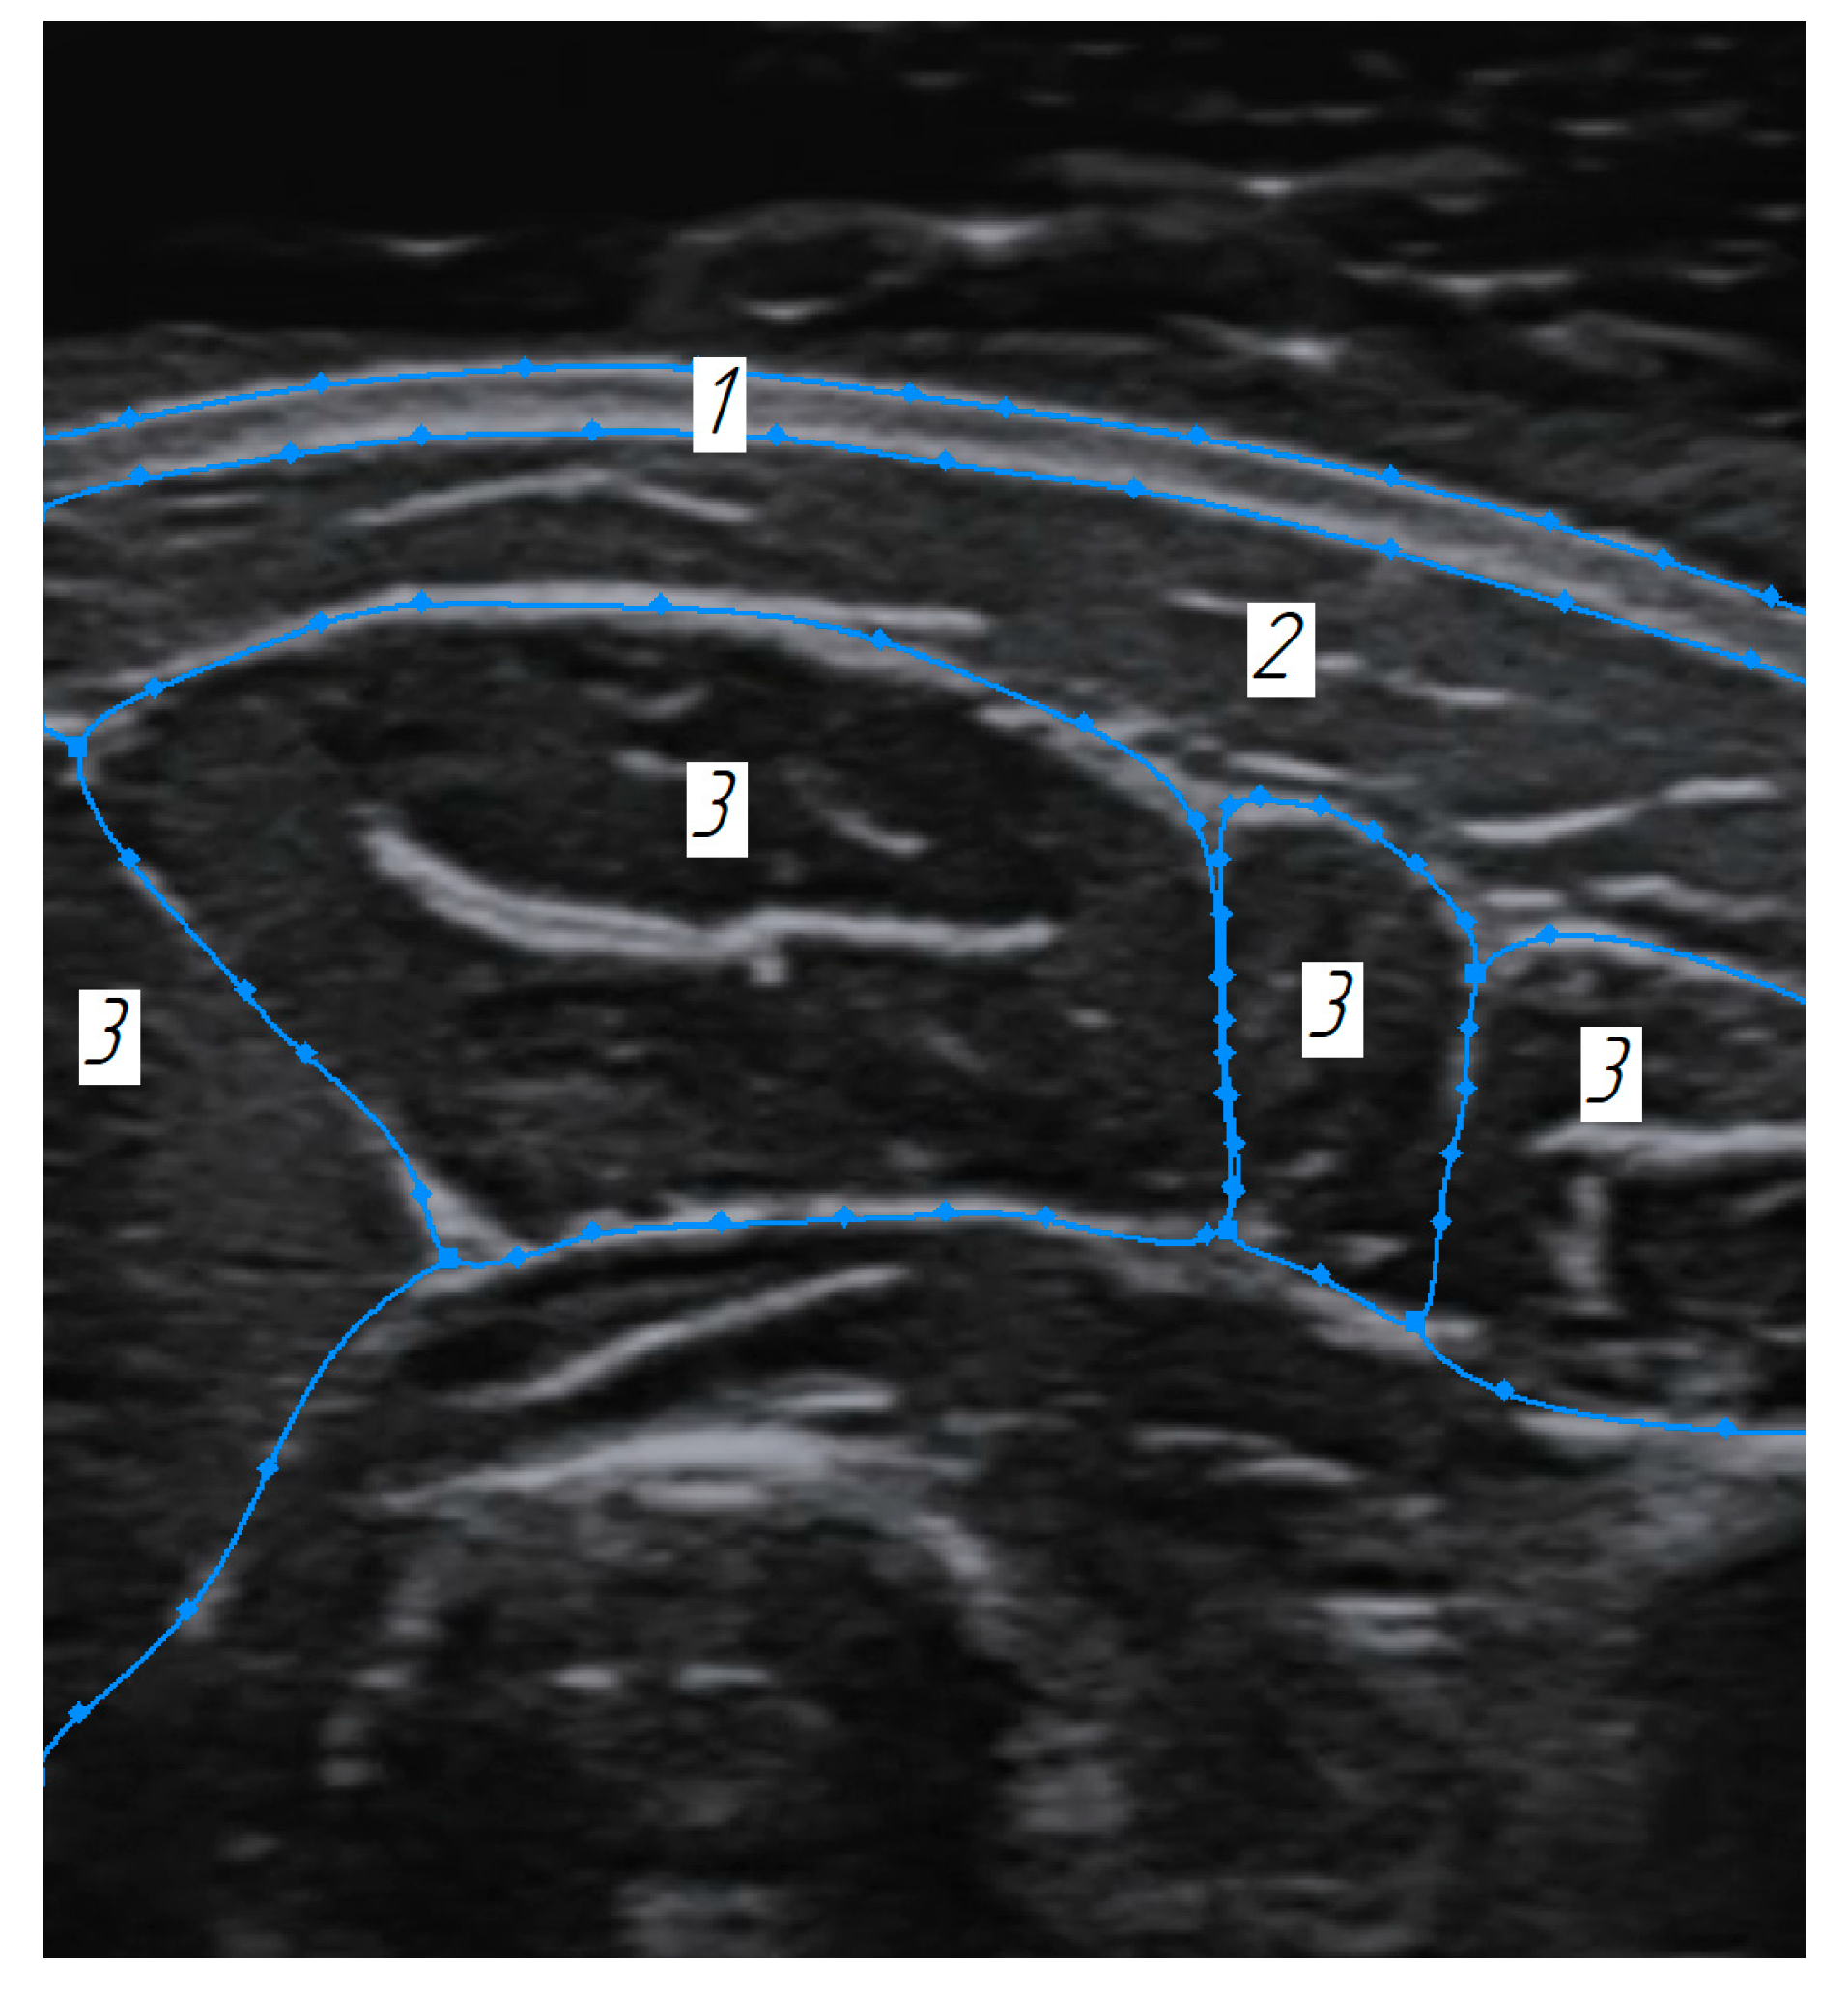

Phantoms imitating biological tissues in their properties are widely used in modern practice [40,41]. In order to verify the method for constructing volumetric models of the soft tissues using ultrasound scanning in an automated mode, a phantom with acoustic properties close to the forearm soft tissues was developed and tested. Sonograms of cross-sections of the forearm in the area of the finger extensor muscle served as initial data for phantom construction (Figure 7).

Figure 7. Sonogram of the cross-section of the forearm: 1—skin layer, 2—subcutaneous fat layer, 3—superficial muscles’ boundaries.

When implementing the method for building the volumetric reconstructed tissue models based on the ultrasound images proposed in this work, it also becomes possible to contour and further volumetrically visualize the surrounding tissues (skin and subcutaneous fat) (Figure 17).

Figure 17. Example of identifying the soft tissue boundaries in the combined ultrasound images: 1—skin layer, 2—subcutaneous fat layer, 3—superficial muscles boundaries.